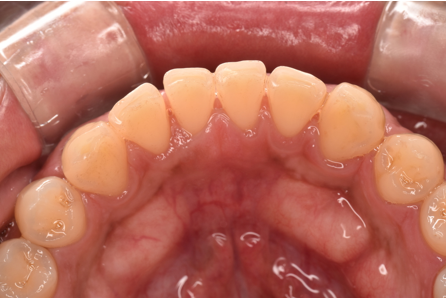

治療前

| カウンセリング・診断結果 | 診察したところ、全体的に歯石が付着していて、特に歯茎の下には黒い歯石が付着していました。 歯茎も赤く腫れており、歯周病の検査を行ったところ、全体的に歯周病が進行し、中等度の歯周炎が認められました。 |